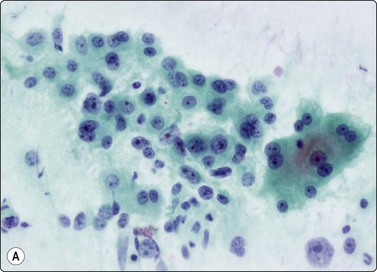

Malignant lymphoma183,184

Liver involvement in stage IV malignant lymphoma portends a poor prognosis and has been found in 25% of random FNA biopsies in patients with lymphoma.185 Primary involvement of the liver is relatively rare. It is often patchy and microscopic and may be missed by either FNA or CNB. The liver tumor may be solitary, multiple or diffuse. Aspirates are usually markedly cellular with dispersed cells and scattered small aggregates without true cohesion, and lymphoglandular bodies are present in the background. Non-Hodgkin lymphoma of diffuse large B cell type (high grade) is the most common type. If on-site rapid evaluation detects a lymphoid lesion, a further needle pass should be performed to obtain cells for phenotyping by immunocytochemistry or flow cytometry, for cytogenetics and for molecular gene rearrangement studies. For detailed cytological criteria for the diagnosis of lymphoma, see Chapter 5. The differential diagnosis of a post-transplant lymphoproliferative disorder (PTLD) should be considered where there is a history of organ transplantation. The smears may be either polymorphous with a mixture of lymphocytes, plasma cells and histiocytes, or monomorphous with large atypical lymphocytes. The diagnosis is supported by identifying B-cell monoclonality and the presence of EBV DNA.183,186,187